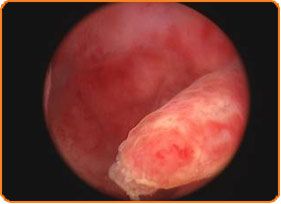

Diagnostic uteroscopy is performed quickly and painlessly, such as a visit for Pap test, and is recorded on video as a medical record. The interior of the uterus, the area of implantation of embryos and fetal hospitality area is now accessible. Its examination with the hysteroscope, namely with direct vision, gives us important information on the factors which contribute to reduced fertility, such as:

- the quality of the endometrium,

- the presence of polyps,

- scars or evidence of inflammation.

- we remove polyps,